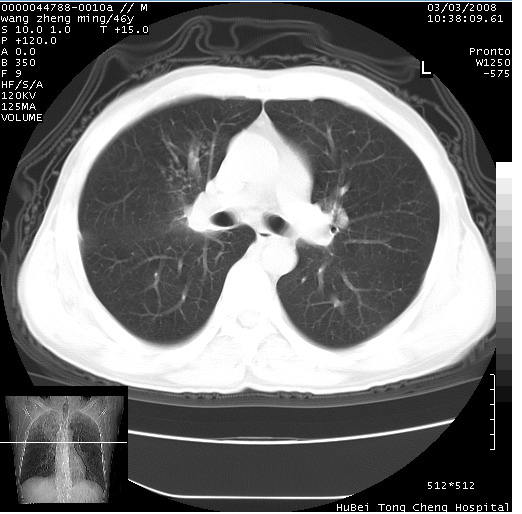

以下是引用卜一在2008-3-22 1:37:00的发言:[br]右肺实质性肿块,边缘不整,明显见毛刺征 分叶征及胸膜凹陷征,右上叶支气管明显变窄,远端散在的片状 斑片状实变影。另:左肺门较大肿块,支气管受累 变窄,远侧见阻塞性肺炎。纵隔内见肿大淋巴结。多考虑:右肺周围性肺癌伴左肺门 纵隔淋巴结转移!